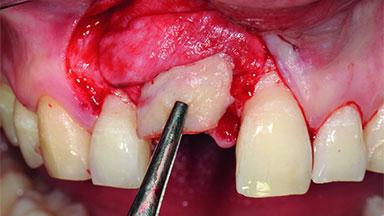

Replacement of a Compromised Upper Right Central Incisor: Hard- and Soft-tissue Augmentation, Late Placement of an RC Bone Level Implant

Bone Augmentation Horizontal|Simultaneous|Staged

Augmentation Materials Xenogenous|Membrane

Bone Volume Deficient horizontally, requiring prior grafting